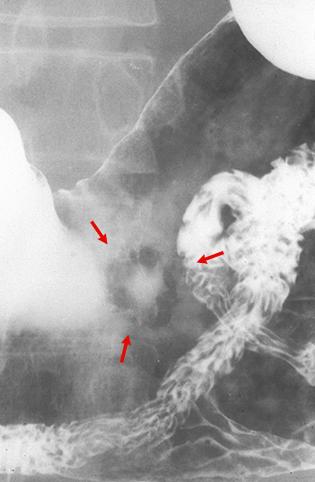

疾病(病理主体)的分类恶性上皮性肿瘤/腺癌

部位(按器官分)胃(部位)/体部

检查方法X线

肿瘤的肉眼分类0型(表在型)/IIa型(IIa+IIc)

肿瘤最大直径15~19

肿瘤的深度sm